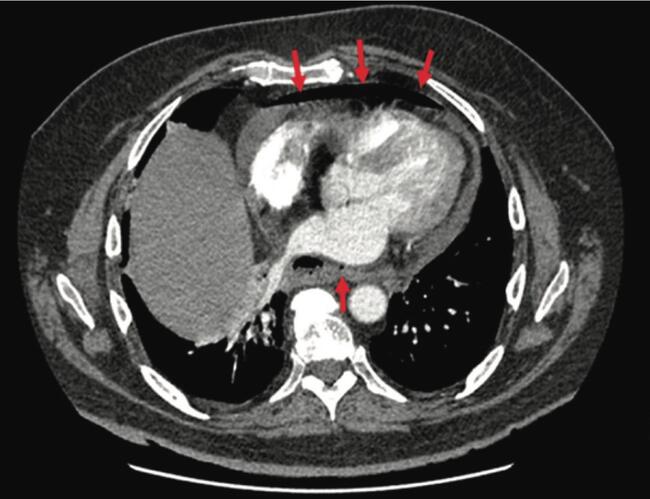

Atrial fibrillation (AF) is the most prevalent arrhythmia in the U.S., affecting over 6 million Americans. AF constitutes a major health concern worldwide owing to its association with impaired quality of life, stroke, heart failure, dementia, and increased mortality.1-3 The ever-growing understanding of the disease allied to constant technical and technological advances has triggered a progressive expansion in the number of AF ablation procedures. As a result, guidelines are being continuously updated to broaden procedural indications based on growing safety data and consistently improved outcomes.4-6 Nevertheless, AF ablation is not risk-free, and ablation-related esophageal thermal injury (ETI) is yet a concern. ETI seems to be more prevalent than previously thought, as “silent” lesions have been found in asymptomatic patients undergoing active post-procedural screening.7 Atrial-esophageal fistula (AEF) remains the most dreaded complication in AF ablation procedures, and although rare, it is associated with high mortality.8